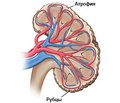

Малик А.І., Зограб’ян Р.О.

ДУ «Національний інститут хірургії та трансплантології ім. О.О. Шалімова» НАМН України, м. Київ, Україна

Журнал «Почки» Том 8, №3, 2019